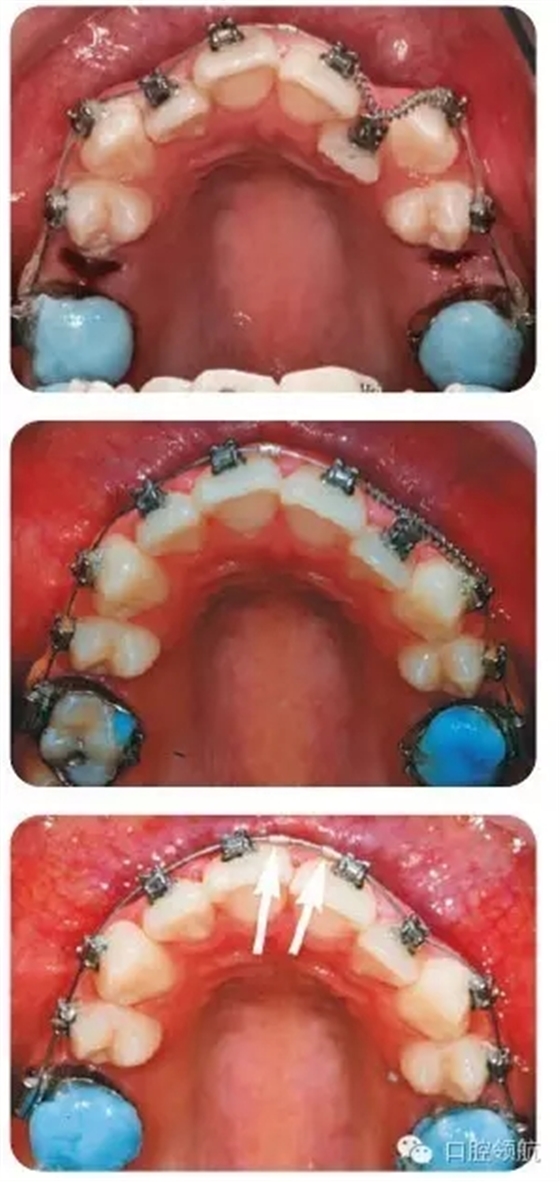

圖3.2中治療措施的說明

拔除上頜雙側(cè)第二前磨牙后,粘結(jié)上頜托槽,使用0.013英寸鎳鈦圓絲,配合UL1、UL3間的鎳鈦推簧,為UL2的納入提供間隙。同時,以上頜第一磨牙為支抗,采用彈性鏈狀結(jié)扎圈拉尖牙向遠中移動。UL2通過結(jié)扎絲懸吊至弓絲上,以促進其唇向移動。由于可能導致的牙弓變形,牙齒傾斜移動以及難以預估的反作用力,我們通常并不推薦在鎳鈦圓絲上使用主動力。但是,有研究指出自鎖托槽穩(wěn)定的鎖結(jié)效果可以有效地規(guī)避上述風險。

圖3.2(第三幅圖)中所示的箭頭是什么?

這是在弓絲上放置的小型金屬停止扣,用以阻止治療初期出現(xiàn)的弓絲滑脫。否則,由于自鎖托槽與弓絲間的滑動摩擦力過小,弓絲可能由一側(cè)滑脫,甚至刺入磨牙后墊造成損傷。

為什么在上頜第一磨牙面放置玻璃離子墊高材料?

這項措施能夠使上下頜脫離咬合接觸,從而有利于糾正UL2鎖。也可以使用活動矯治器或固定的咬合打開裝置達到此目的。